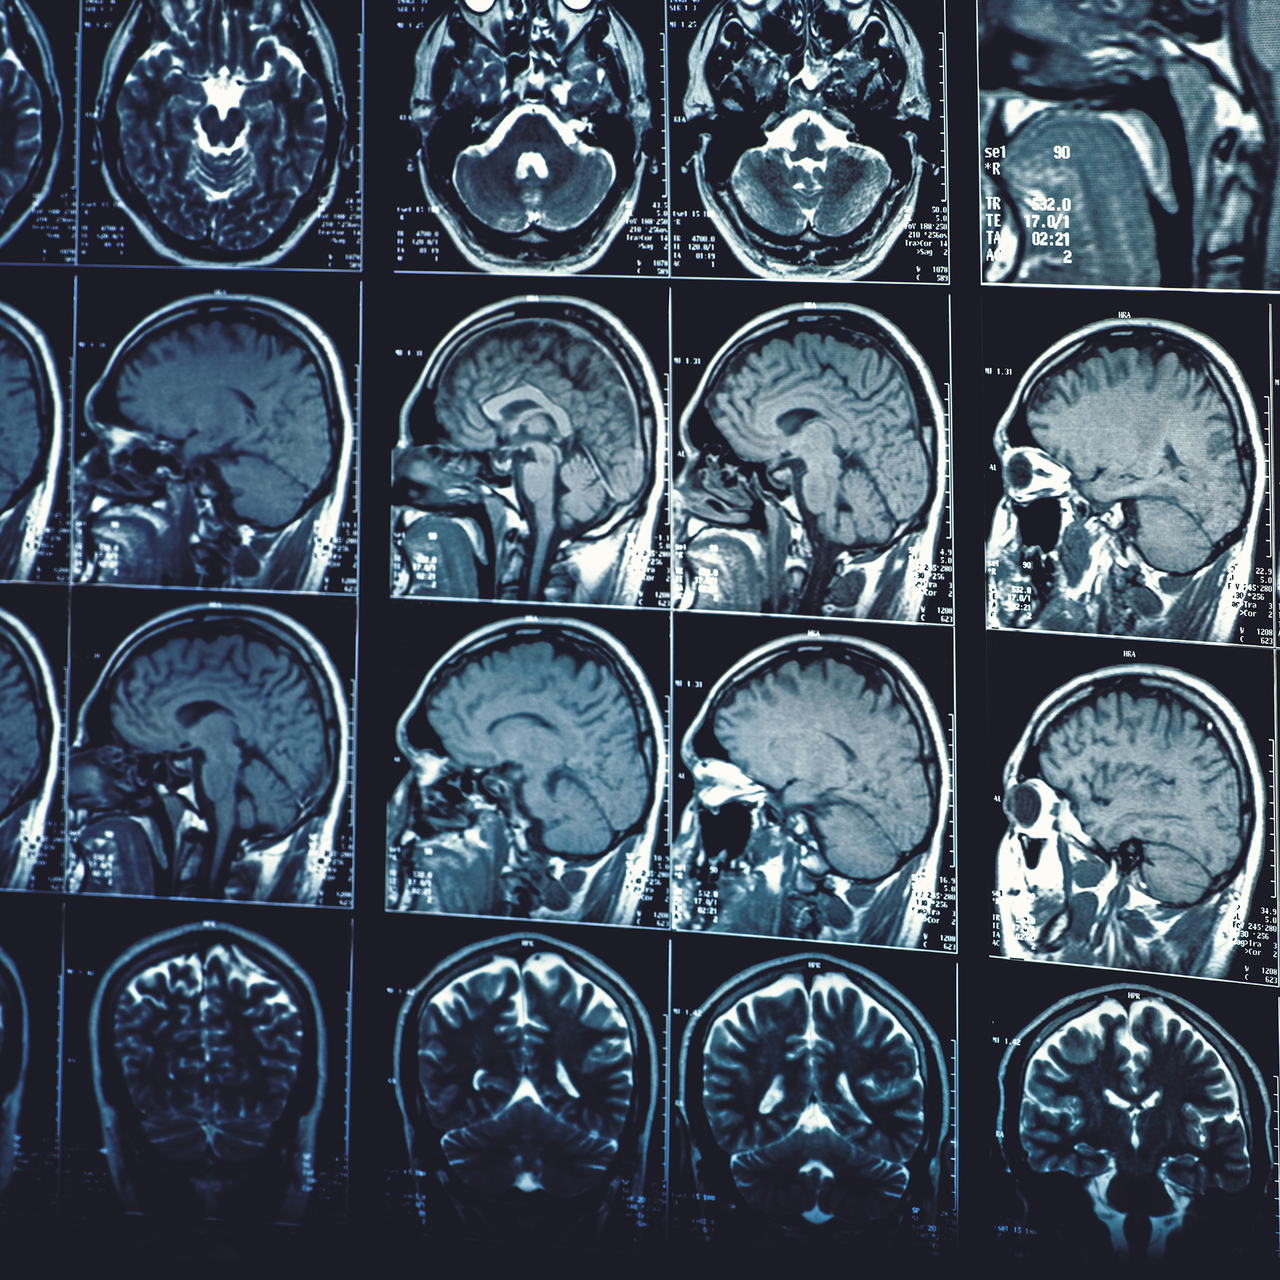

Ondokuz Mayıs Üniversitesi (OMÜ) Tıp Fakültesi Nöroloji Anabilim Dalı ve Türk Nöroloji Derneği Başkanı Prof. Dr. Murat Terzi, yaptıkları çalışmalarla yapay zekanın nörolojik hastalıkların tanısında yüzde 90'ın üzerinde doğru bir tanı verdiğini ve yapay zekayı eğitmeye devam ettiklerini söyledi